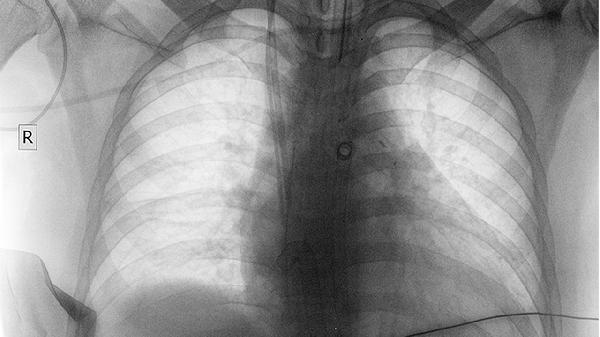

体检发现肺部阴影不一定是肿瘤,可能是炎症、结核、肺纤维化、肺血管异常或良性结节等引起。肺部阴影的性质需结合影像特征、病史及进一步检查综合判断。

炎症性阴影多由细菌或病毒感染导致,常见于肺炎、支气管扩张等疾病,CT可见斑片状模糊影,部分伴有发热咳嗽症状,需进行血常规、痰培养等检查,治疗可选用阿莫西林克拉维酸钾片、左氧氟沙星片、头孢呋辛酯片等药物。结核性阴影表现为上肺野结节或空洞,伴随低热盗汗,结核菌素试验和痰涂片可辅助诊断,需规范使用异烟肼片、利福平胶囊、吡嗪酰胺片等抗结核药物。肺血管异常如肺栓塞或血管畸形,CT可见楔形梗死灶或血管迂曲,D-二聚体检测和肺动脉造影可确诊,需根据病情选择抗凝或介入治疗。

肿瘤性阴影需高度警惕,恶性肿瘤多呈分叶状或毛刺征,增长较快,可通过增强CT、PET-CT或穿刺活检明确,早期肺癌可行胸腔镜手术切除。良性肿瘤如错构瘤边缘光滑,生长缓慢,定期随访即可。肺纤维化阴影呈网格状改变,多见于尘肺或特发性间质性肺炎,肺功能检查显示限制性通气障碍,治疗以糖皮质激素和抗纤维化药物为主。发现阴影后应避免吸烟及接触粉尘,保持室内通风,出现咯血或持续胸痛需立即就诊。

建议发现肺部阴影后及时到呼吸内科或胸外科就诊,完善肿瘤标志物、支气管镜等检查。日常需戒烟并避免二手烟,雾霾天气减少外出,适当进行有氧运动增强肺功能,饮食注意补充优质蛋白和维生素A,定期复查胸部CT观察阴影变化。